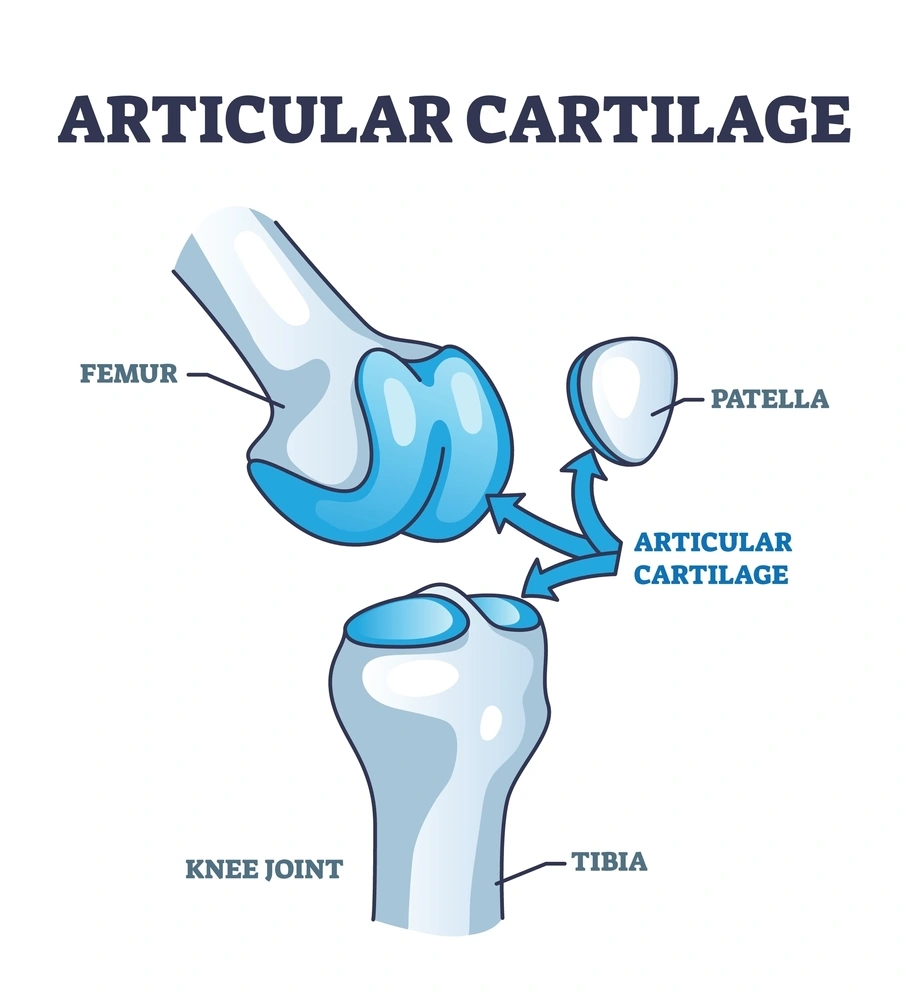

Articular cartilage repair is a specialized orthopedic procedure that restores damaged cartilage in joints such as the knee, hip, or ankle, enabling smooth, pain-free movement. Cartilage acts as a cushion between bones, facilitating effortless joint motion and absorbing impact, but once injured or degenerated, it does not heal naturally, leading to pain, stiffness, and reduced mobility. Our expert surgeons employ advanced regenerative and surgical techniques — including microfracture surgery, autologous chondrocyte implantation (ACI), and osteochondral grafting — to repair or replace damaged cartilage, preserving natural joint function and preventing progression to arthritis. Each treatment is personalized based on the extent of damage, patient age, activity level, and joint health.

Cartilage repair alleviates joint pain, restores flexibility, and improves overall mobility, allowing patients to return to active lifestyles and daily activities with comfort. Unlike joint replacement, these procedures aim to regenerate natural cartilage and preserve the patient’s own joint, making them particularly suitable for younger or highly active individuals. In addition to reducing discomfort, cartilage repair can prevent further joint deterioration, delay the need for joint replacement, and enhance long-term joint health, providing patients with lasting functional and emotional benefits.

Cartilage repair procedures are often minimally invasive, performed through small arthroscopic incisions using advanced imaging and surgical navigation systems. Microfracture surgery stimulates new cartilage growth by creating small holes in the underlying bone, while ACI involves growing healthy cartilage cells in a lab before implanting them in the damaged area. Osteochondral grafting replaces damaged tissue with healthy cartilage and bone from the patient or donor. Recovery includes early physical therapy to restore strength, flexibility, and range of motion, with gradual progression of weight-bearing under professional supervision. Most patients experience significant improvement in function and reduction in pain within weeks to months, depending on the procedure and extent of damage.